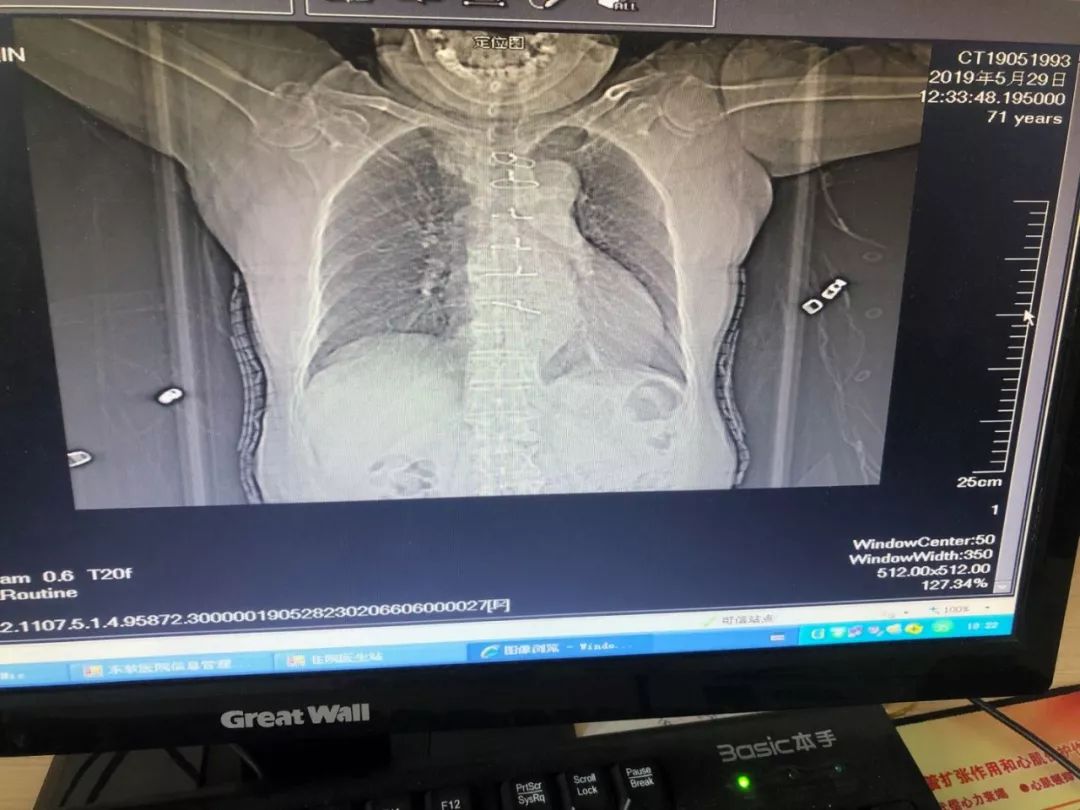

71岁的轩奶奶因“升主动脉瘤”于今年5月份在北京进行手术治疗,一次开胸手术留下的长长伤口不只让轩奶奶身体承受了巨大的痛苦,心理更增加了负担,这次大手术后一定要好好静养,这一养不要紧,心脏越来越难受,胸闷气短,还恶心。家属赶紧带轩奶奶来医院检查,经我院常务副院长、心脏中心主任张占修检查后,轩奶奶这明显就是术后没有进行康复治疗,所以导致恢复不好,而且还伴有心衰和肺炎,于是建议收入我院心脏康复中心。经过一周的伤口护理、对症治疗和心脏康复,轩奶奶恢复良好,呼吸顺畅。